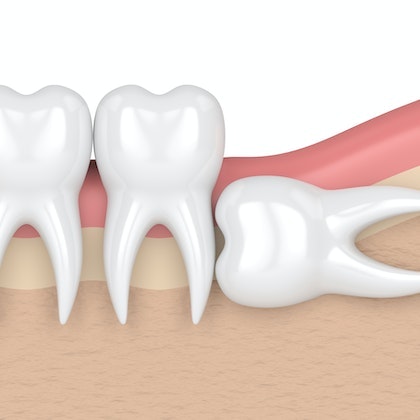

Take a Look

AT HOW WISDOM TEETH CAN CAUSE OVERCROWDING

In many cases, the small size of the jaw can become an issue when the wisdom teeth begin to come in. Even if the wisdom teeth erupt properly, they can cause your other teeth to shift. This can lead to misaligned teeth, which can also cause pain in the temporomandibular joints (TMJs). Extraction can prevent these issues.